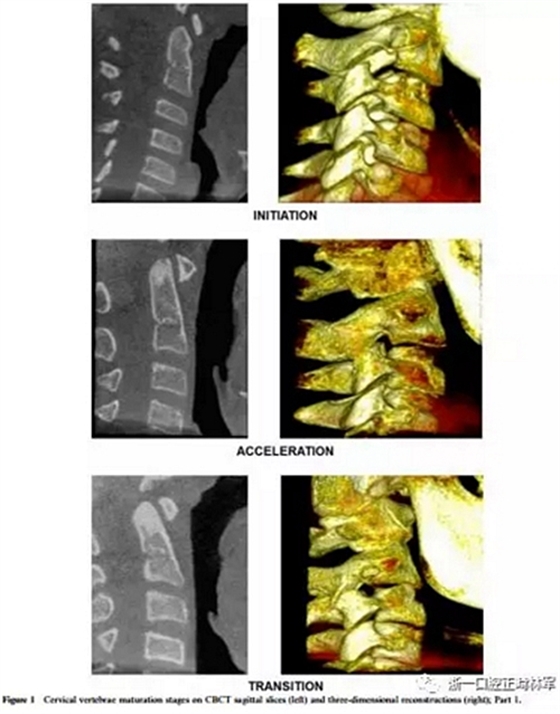

將CBCT三維重建和矢狀切片隨機(jī)分組,并使用軟件OsiriX®(The Osirix Foundation,Geneva,Switzerland)評估兩次。這些圖像在MacBook Pro(Apple Computer Inc.,Cupertino, CA)。使用OsiriX軟件,通過使用三維成像技術(shù),從醫(yī)學(xué)文件中的數(shù)字成像和通信獲得三維圖像重建。通過多平面重組獲得的矢狀切面是通過將光標(biāo)定位在沿中腭縫線和前鼻棘中心的線上來選擇的。為了避免視疲勞,每天只評估20幅圖像。評估分階段進(jìn)行,每次選擇一種展覽模式,第一次和第二次。CBCT圖像在昏暗的房間里,在具有亮度和對比度恒定特征的屏幕上進(jìn)行解讀,允許利用軟件的縮放,亮度和對比度工具來增強(qiáng)診斷。每個(gè)展覽模式的圖像解讀最短時(shí)間為15天。在第一次評估后1個(gè)月,考慮到3D重建和矢狀切片(圖1和圖2),讀片員再次讀片,獲取72條記錄。

椎骨C2,C3和C4的分類方法分為六個(gè)階段,可以描述如下:

1、初期(頸椎成熟指數(shù)-1)

這對應(yīng)于青春期生長噴發(fā)(PGS)的初始階段,其中預(yù)期有80-100%的增長。椎骨的下邊界是平坦的。在C3和C4的上邊界有一個(gè)從后向前的斜坡。

2、加速期(頸椎成熟指數(shù)-2)

這個(gè)階段接近PGS峰值,預(yù)計(jì)增長率為65-85%。椎骨C2和C3的下邊界呈現(xiàn)一個(gè)小的凹陷,這在C4上仍然是平坦的。 C3和C4的體部呈矩形。

3、過渡期(頸椎成熟指數(shù)-3)

這對應(yīng)于個(gè)人的高峰增長,預(yù)計(jì)增長25-65%。 C2和C3的邊界呈現(xiàn)出不同的凹陷,這在C4上很微小。椎骨C3和C4的體部是矩形的。